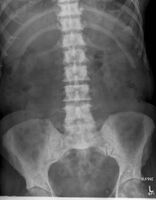

Prostate cancer that has metastasized to the lymph nodes

Prostate cancer that has metastasized to the bone